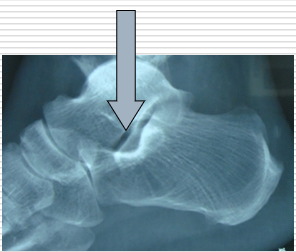

跟骨骨折为临床常见病,发病率高,占跗骨骨折的60%,全身骨折的2%。 跟骨骨折治疗困难,预后差。 治疗方案个体化强,方法多种多样。 跟骨骨折后,形态发生复杂的变化,包括G角、B角、宽度、高度、后关节面的对合情况等等。

跟骨的解剖学标志,最重要的就是两个角度

Bohler’s角:缩小、消失或反角,反映后关节面的塌陷Gissan‘s角:反映跟距关节内骨折的严重程度